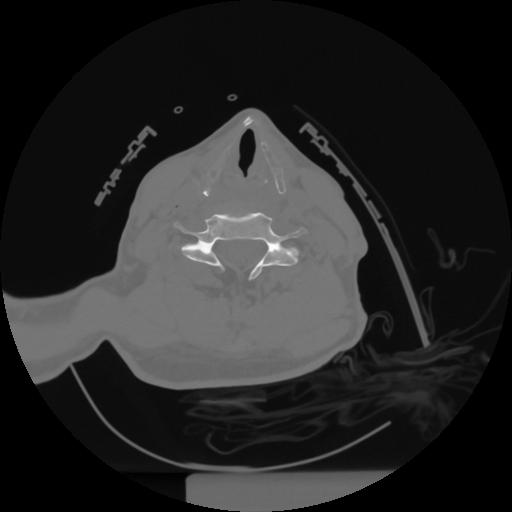

12 P.BLANDAS,,Vol,0.5,P.BLANDAS,,